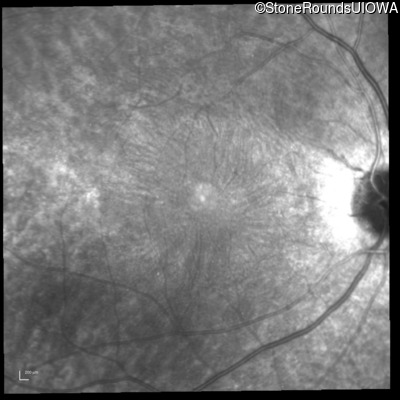

Infrared Fundus Photograph - Right -

20/20 -1

Infrared Fundus Photograph - Left -

20/20 -2